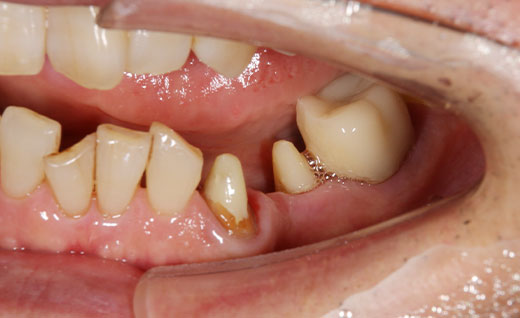

施術前

左下3番目から5番目に保険適応の治療をされておられたのですが、金属が目立ち見た目も良くないという事で今回ジルコニアによるブリッジを施術させていただきました。